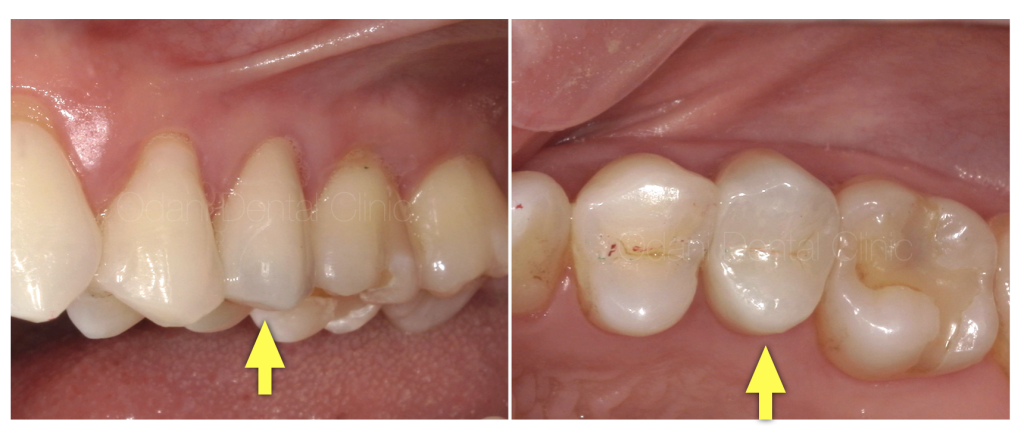

実際にはこのように色合わせのための写真撮影を行い、技工士と共有することで、

これくらい色調表現が可能になります。

※周りの歯の色調により、調和しやすい場合とそうでない場合があります。審美的結果を最優先する場合は、奥歯でもセラミック修復をお勧めしております。